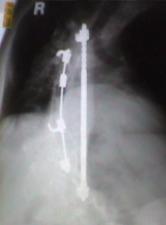

Harrington rods

Despite the risks, I had spinal fusion surgery in April 1966.

During this procedure, two metal rods, called Harrington rods,were attached to

vertebrae in my back to hold my spine in place and prevent it from curving further.